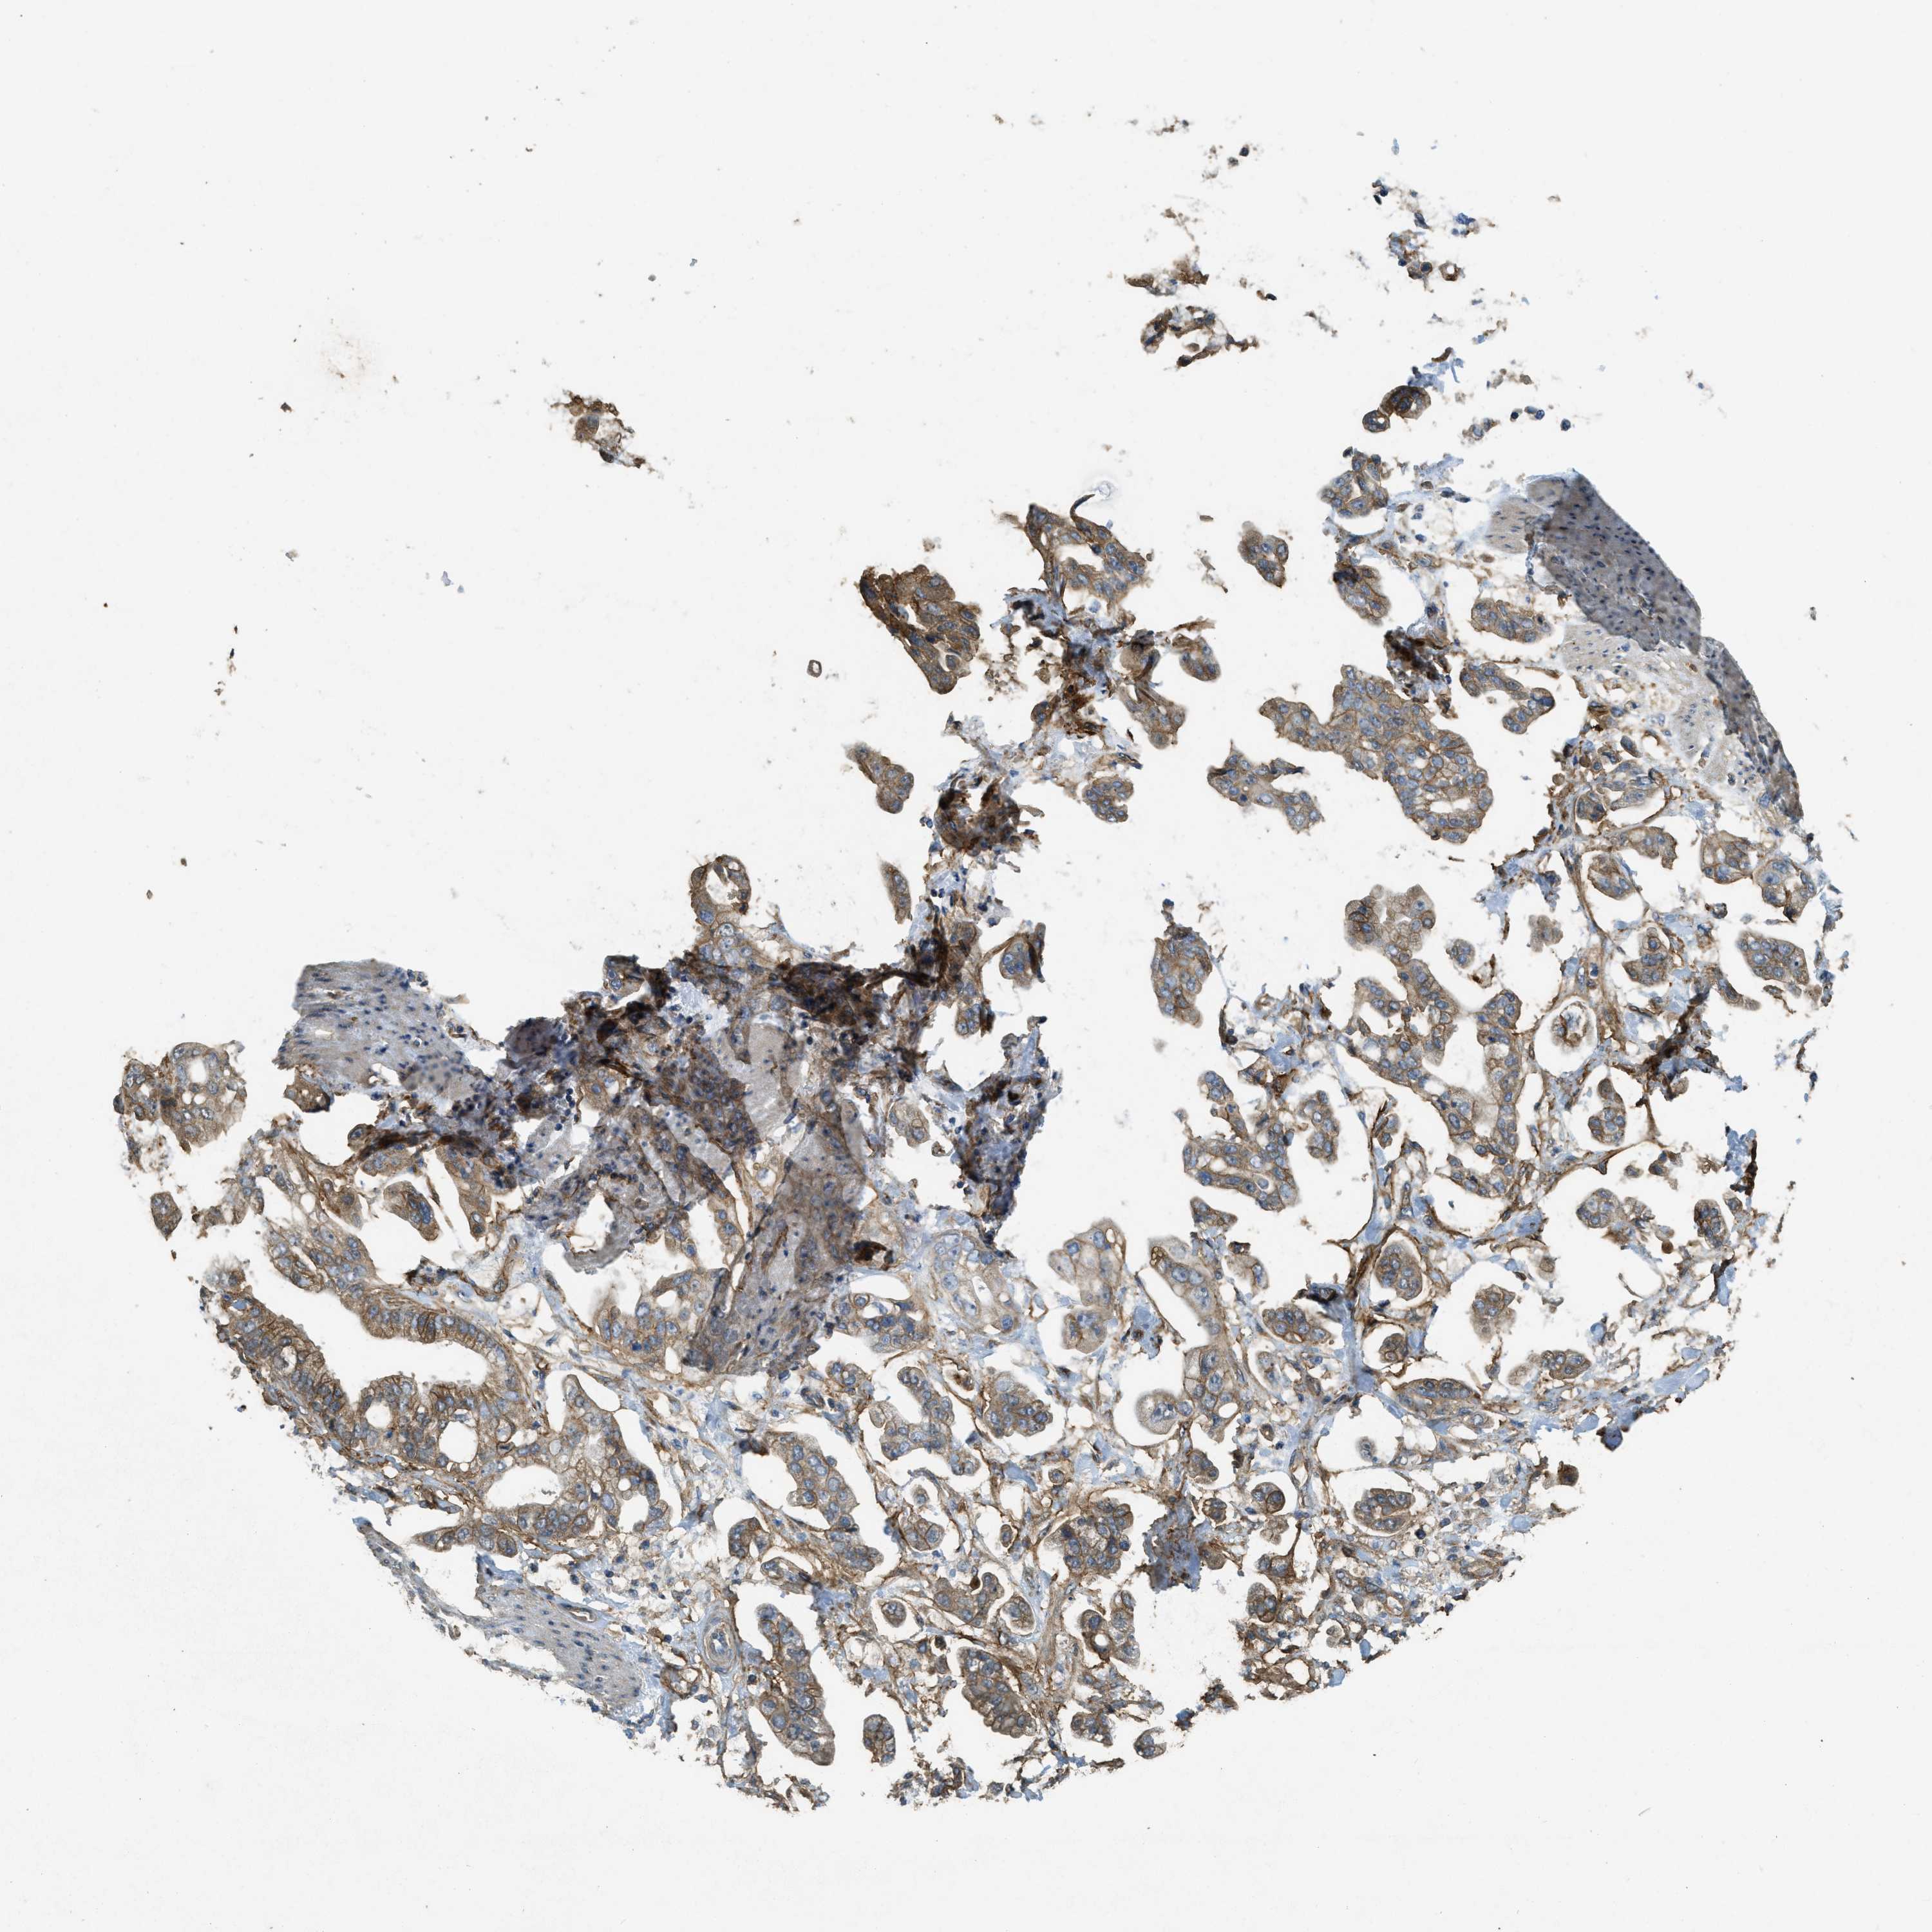

STOMACH CANCER - Protein expressioni

A mouse-over function shows sample information and annotation data. Click on an image to view it in a full screen mode. Samples can be filtered based on level of antibody staining by selecting one or several of the following categories: high, medium, low and not detected. The assay and annotation is described here.

Note that samples used for immunohistochemistry by the Human Protein Atlas do not correspond to samples in the TCGA dataset.

Antibody stainingi

Antibody staining in the annotated cell types in the current human tissue is reported as not detected, low, medium, or high, based on conventional immunohistochemistry profiling in selected tissues. This score is based on the combination of the staining intensity and fraction of stained cells.

Each image is clickable and will lead to virtual microscopy that enables deeper exploration of all samples and also displays staining intensity scores, fraction scores and subcellular localization as well as patient and tissue information for each sample.

Antibody HPA009285

Antibody HPA017139

Antibody CAB017826

Staining

High

Medium

Low

Not detected

Intensity

Strong

Moderate

Weak

Negative

Quantity

>75%

75%-25%

<25%

None

Location

Nuclear

Cytoplasmic/membranous

Cytoplasmic/membranous,nuclear

Adenocarcinoma, NOS

Adenocarcinoma, High grade